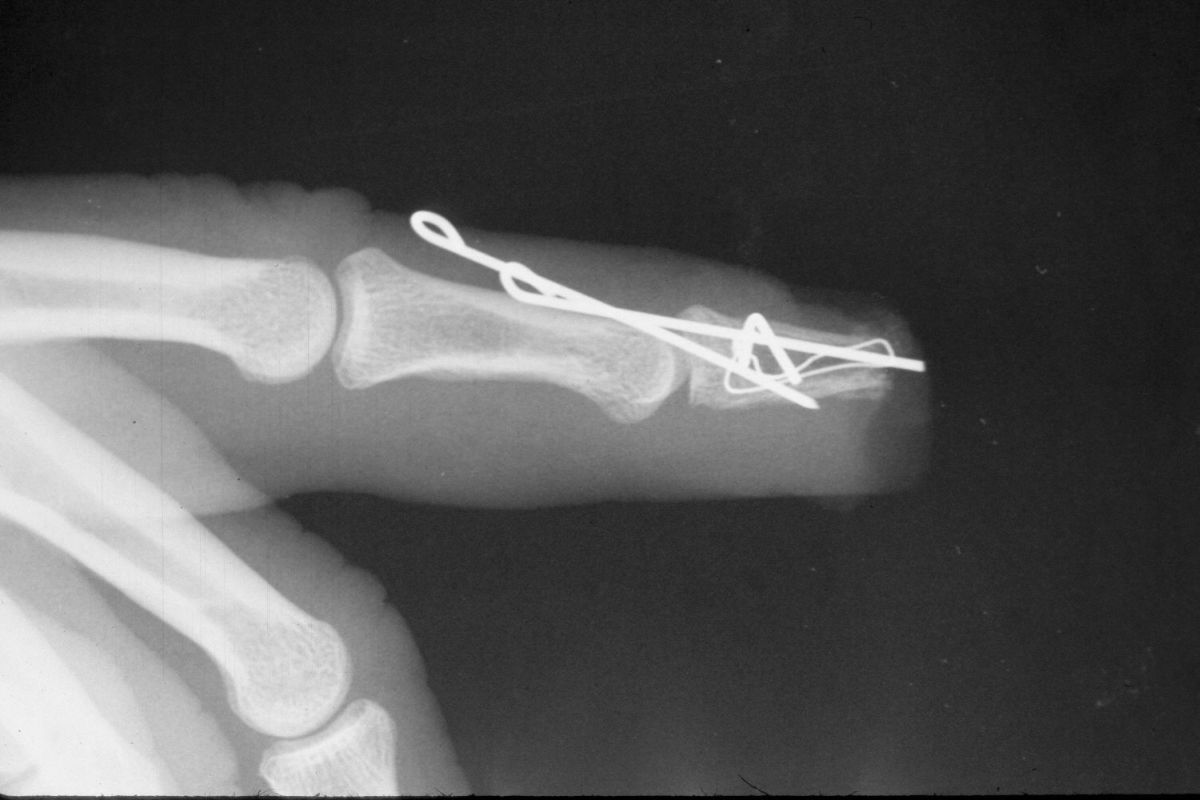

| Distal phalanx

fracture stabilization. Pins were placed to protrude

proximally in anticipation of flap cover. |